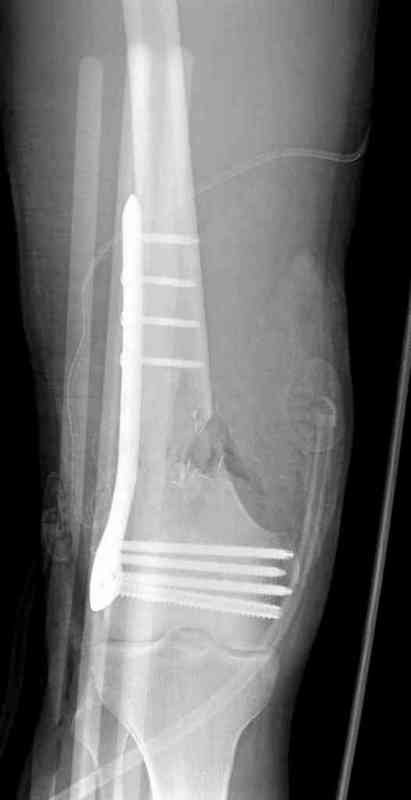

Пострадавшему 23, пистолетная огнестрельная не кроветочащая рана, меньше одного см диаметром, входное отверстие расположено латерально, и выход передне-медиально, и еще имеется второе пулевое ранение правой navicular bone с этой стороны.

Доступ был латеральный, при вскрытии с задней

поверхности бедра обнаружили кровотечение. Поднятием давления на заранее установленном турникете на конечности проконтролировали кровотечение.

В данном случае мы не ставили осуществление гемостаза приоритетным, после 30 минут больной оставлен вызванному сосудистому хирургу со стабильной фиксацией бедра. Несмотря на выбранный передне-медиальный доступ, хирург произвел восстановление сосудистого повреждения.

Латерально пластину защитили ушиванием

илио-тибиального тракта, а медиальная сторона была ушита мышцей, и все раны закрыли ваккумированием (VAC)

На третий день после Irrigation & Debridment закрыли все раны за исключением компартментальной раны из-за отека, медиально в дефект кости установили Putty Grafton Bone Substitute. На компартментальную рану вакуум и мероприятия по сближению краев раны резиновой стяжкой.

На 9й день с момента травмы ушили рану без натяжения. Больной получает реабилитацию, движения коленного сустава с помощи CPM-continuous passive motion machine. Сегодня выписан.